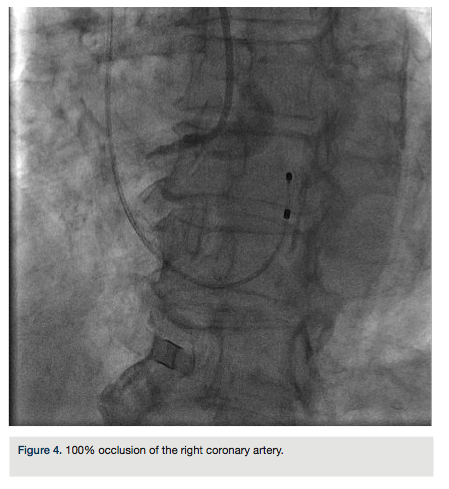

An 84-year-old female with a history of hypertension, diabetes, and dyslipidemia presented to the emergency department with approximately one hour of chest pain and dizziness. Initial electrocardiogram (EKG) demonstrated ST elevations with complete heart block (Figure 1). She was brought to the lab for emergent cardiac catheterization. Diagnostic angiography and percutaneous coronary intervention (PCI) were performed via the right radial artery. A transvenous pacemaker was inserted from the right antecubital vein.

The right radial artery was prepped and draped in sterile fashion, then accessed with a 6 French (Fr) Glidesheath (Terumo). The right antecubital vein was accessed by the nurse prior to the patient’s arrival to the lab and changed (after sterile prep followed by betadine solution) to a 5 Fr Glidesheath (Figure 2). The transvenous pacemaker was advanced  into the right ventricle (Figure 3). Following placement of the pacemaker and capture, a Judkins right (JR) 4 6 Fr guide was used to engage the right coronary artery. Angiography demonstrated a proximal right coronary artery occlusion with TIMI-0 flow (Figure 4). After administration of bivalirudin (Angiomax, The Medicines Company), a Runthrough wire (Terumo) was passed distally. A 1.0 x 10 mm ClearWay balloon (Atrium Medical) was advanced to the lesion and intracoronary abciximab (ReoPro, Eli Lilly & Co.) was administered. Following drug administration, there was improved flow and evidence of a more focal obstruction (Figure 5). A 3.0 x 15 mm Integrity bare metal stent (Medtronic) was deployed at 11 atm with no angiographic residual stenosis and restoration of TIMI-3 flow (Figure 6).  Following revascularization of the right coronary artery, the guide was advanced into the left ventricle to calculate the left ventricular end diastolic pressure (LVEDP) and perform ventriculography (estimated ejection fraction was 55% with mild inferobasal hypokinesis noted on hand injection.  No significant transvalvular gradient was noted on pull-back). A diagnostic Judkins left (JL) 3.5 catheter was then used to engage the left coronary system. Angiography revealed a 90% proximal left anterior descending coronary artery (LAD) stenosis and intermediate disease of the circumflex (Figure 7).  The patient was started on ticagrelor (Brilinta, AstraZeneca) and aspirin, and transferred to the unit. The pacemaker was removed after the patient regained sinus rhythm. She was discharged home after 48 hours with plans for staged intervention of the LAD.